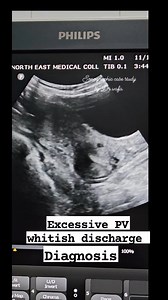

#sonographiccasestudy #reelsvideo #reelsvideoシ #education #ultrasound #Radiology #fblifestyle | Sonographic case study

Facebook

Sonographic case study

視聴回数: 2.1万 回

3 か月前